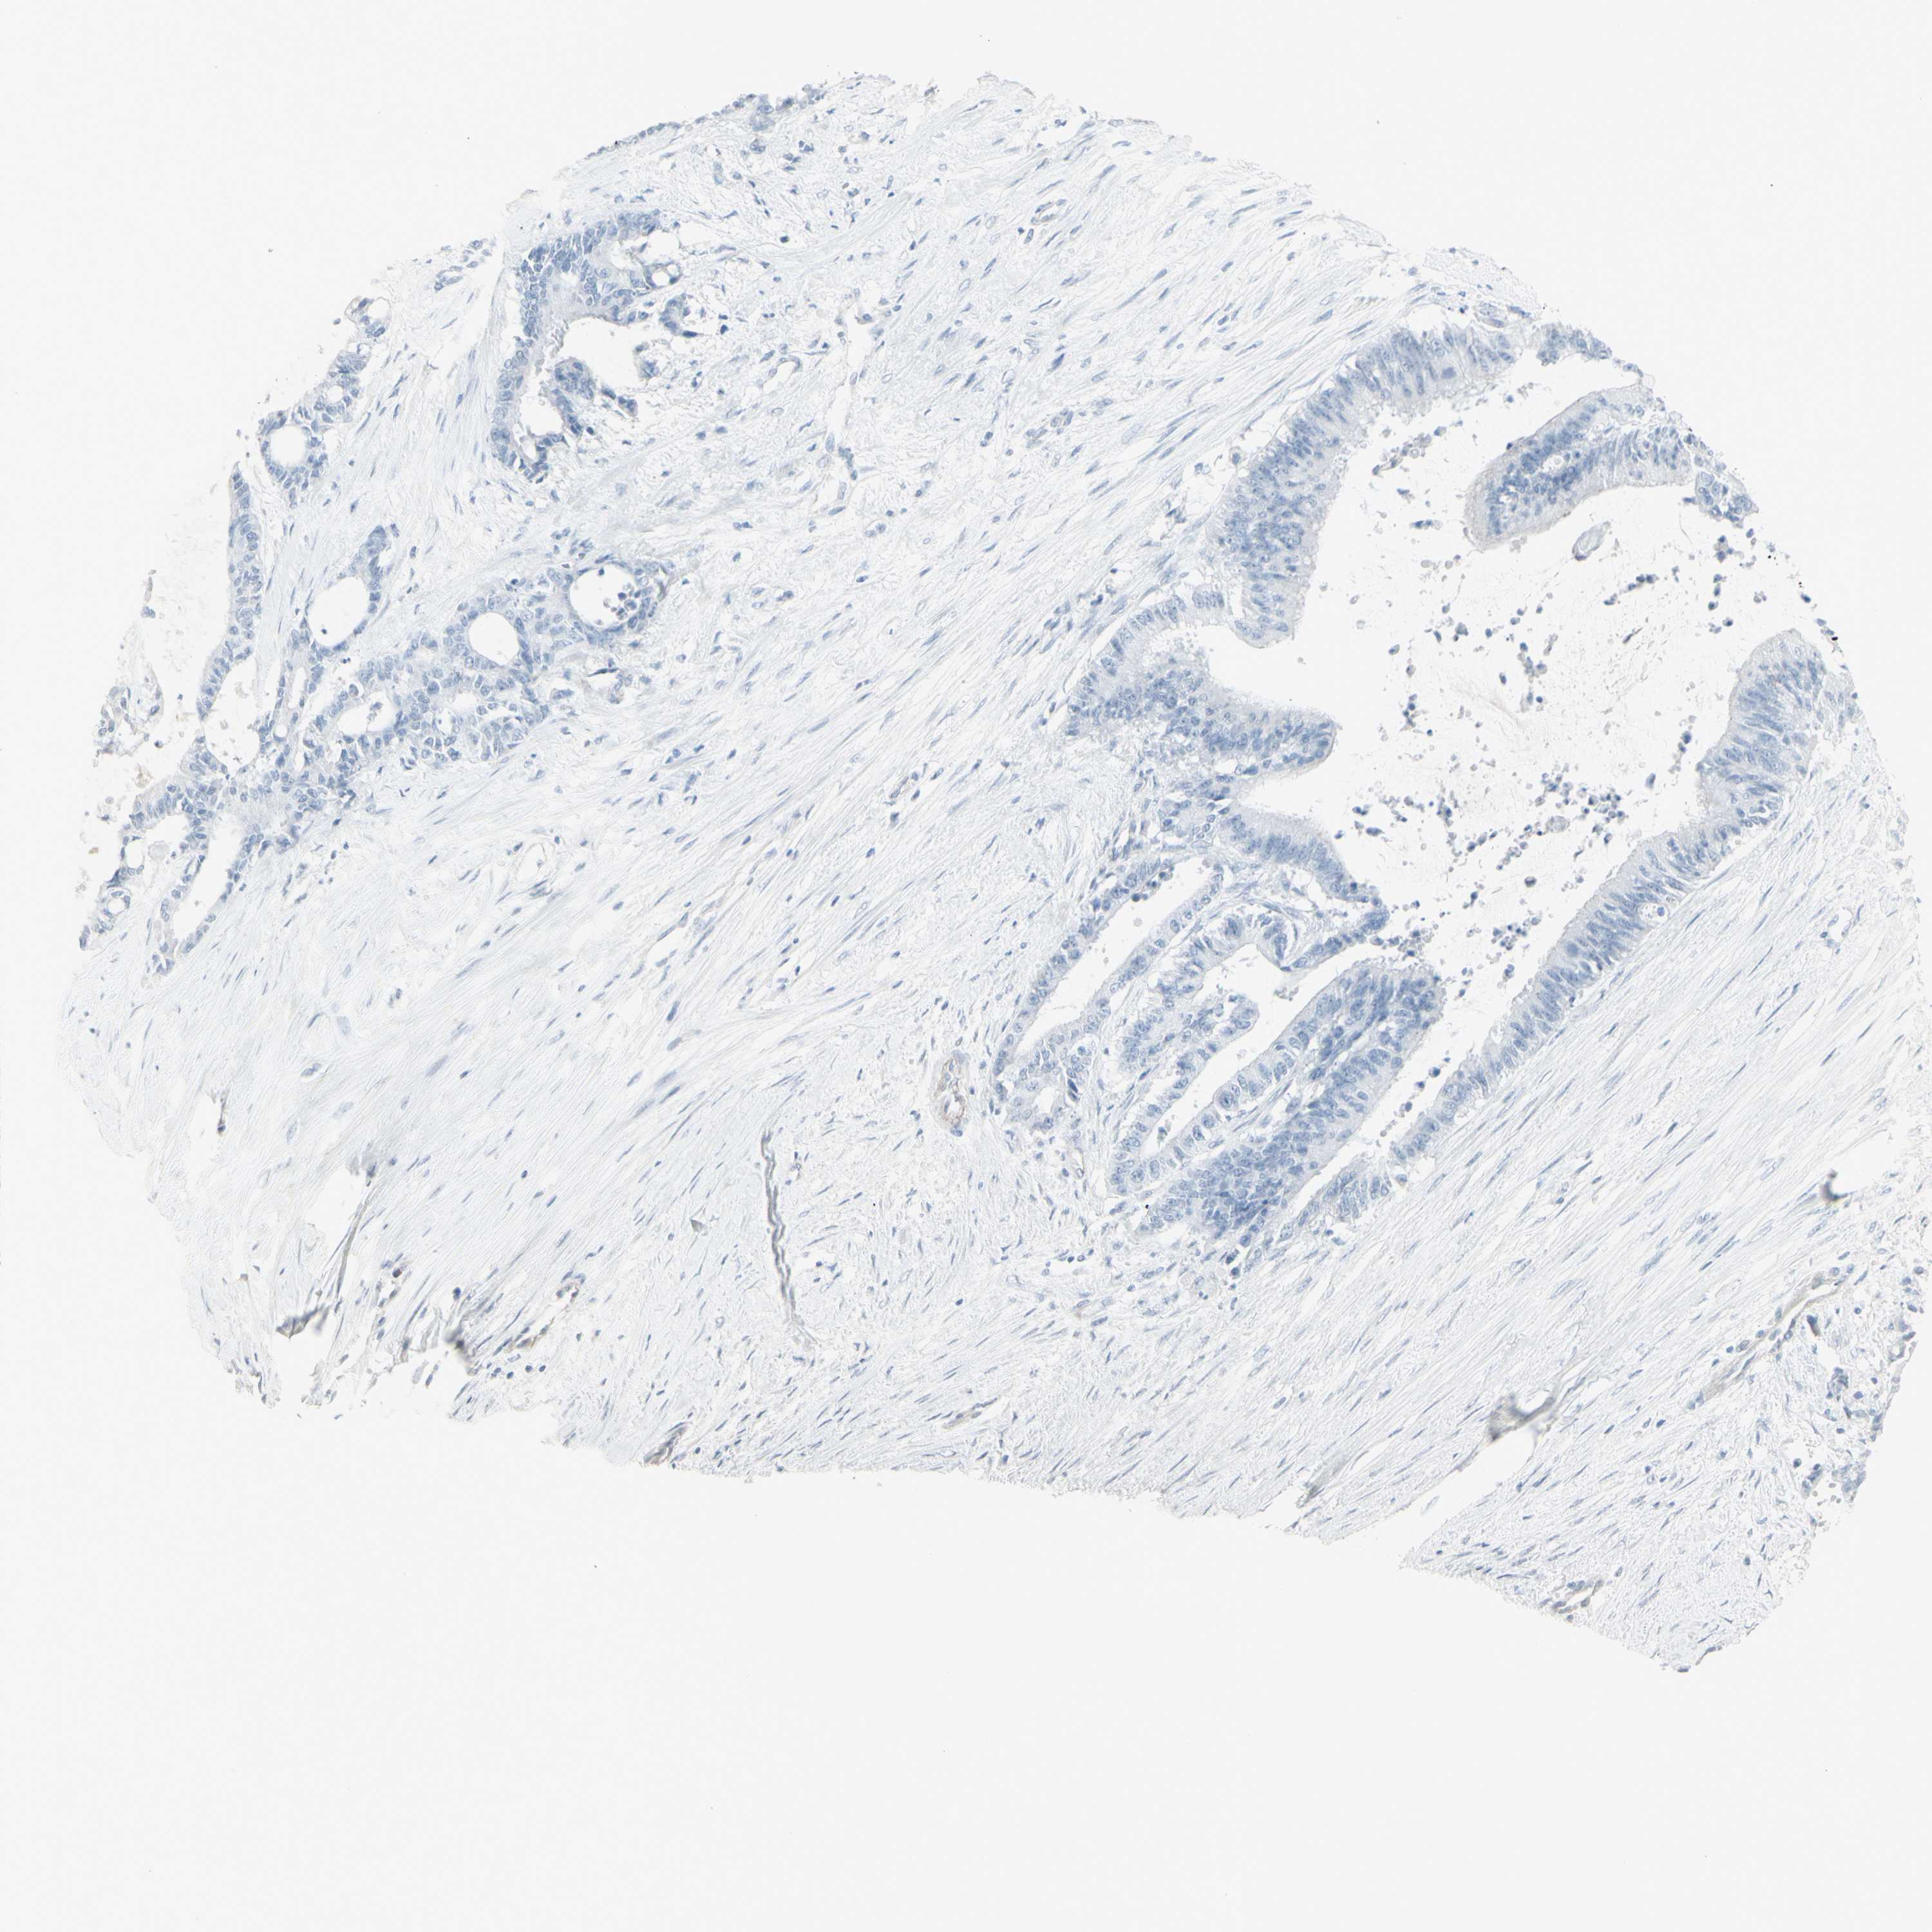

LIVER CANCER - Protein expressioni

A mouse-over function shows sample information and annotation data. Click on an image to view it in a full screen mode. Samples can be filtered based on level of antibody staining by selecting one or several of the following categories: high, medium, low and not detected. The assay and annotation is described here.

Note that samples used for immunohistochemistry by the Human Protein Atlas do not correspond to samples in the TCGA dataset.

Antibody stainingi

Antibody staining in the annotated cell types in the current human tissue is reported as not detected, low, medium, or high, based on conventional immunohistochemistry profiling in selected tissues. This score is based on the combination of the staining intensity and fraction of stained cells.

Each image is clickable and will lead to virtual microscopy that enables deeper exploration of all samples and also displays staining intensity scores, fraction scores and subcellular localization as well as patient and tissue information for each sample.

Antibody HPA053904

Antibody HPA056744

Antibody CAB012332

Staining

High

Medium

Low

Not detected

Intensity

Strong

Moderate

Weak

Negative

Quantity

>75%

75%-25%

<25%

None

Location

Nuclear

Cytoplasmic/membranous

Cytoplasmic/membranous,nuclear

Carcinoma, Hepatocellular, NOS

Cholangiocarcinoma